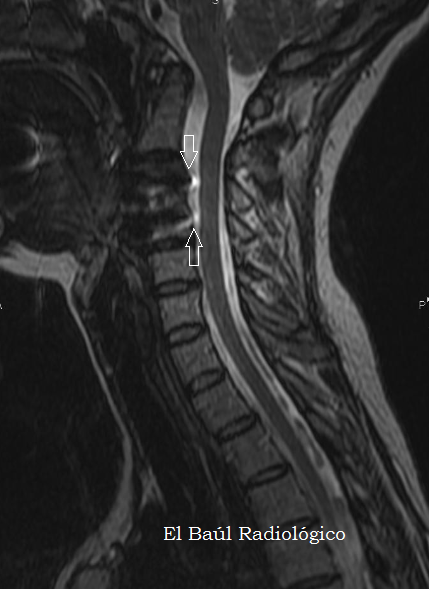

Artrodesis+cervical+2.png

FIGURA 5) Secuencia FSE-T2. La placa metálica de titanio produce artefactos mayores  que en las imágenes FSE-T1 (flechas).

(FSE-T2 MRI Sequence. The titanium metal plate produces, black and white, magnetic susceptibility artifacts (arrows).